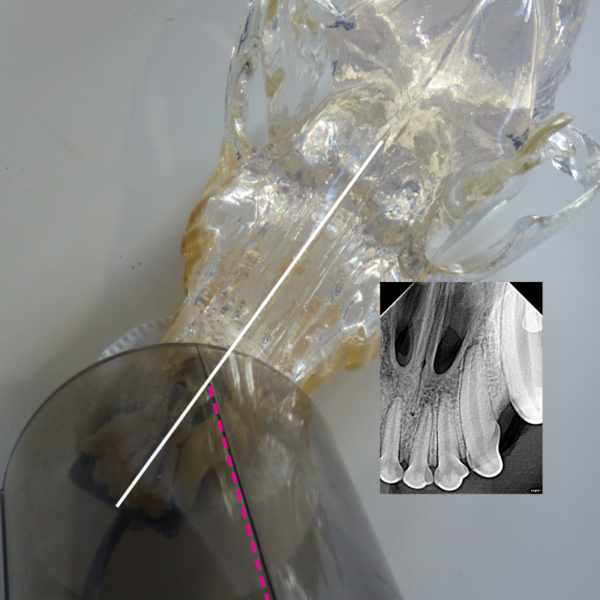

Dental XRay Positioning Guide Canine Mandibular Premolar 309 D.A.V.I Dental X Ray Positioning Guide Canine Dental radiograph positioning “cheat sheet” introduction: This will guide you through how to position the tube head, where to put your sensor, what angle to use for every single position that you will. For the mandibular canines and incisors, it's possible to get them into one shot, but to radiograph the canine tooth alone, place the sensor with the leading. Dental X Ray Positioning Guide Canine.

Dental XRay Positioning Guide Canine Mandibular Premolar 309 D.A.V.I Dental X Ray Positioning Guide Canine *think of dental radiographs as a “shadow” of the root of the tooth* *you need. Dental radiograph positioning “cheat sheet” introduction: For the mandibular canines and incisors, it's possible to get them into one shot, but to radiograph the canine tooth alone, place the sensor with the leading edge at the canine tooth,. Place the patient in dorsal. To properly. Dental X Ray Positioning Guide Canine.